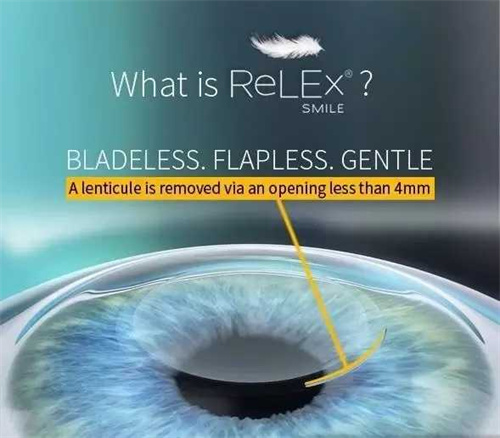

特色技术:医院开展的微切口超声乳化手术,切口仅1.8mm,术后改善比较快,第二天即可获得良好视力。